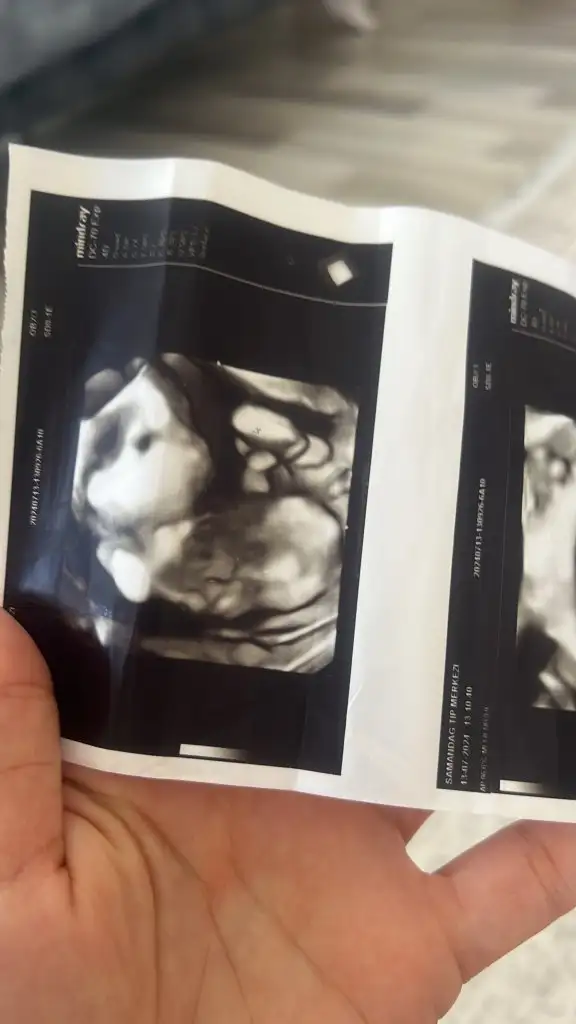

Merhaba arkadaşlar 12 haftalık ultrason fotoğrafı

Tahminde bulunacak olan varmı 🥲🙏🌸❤️

• A6B01867-FBE0-4C1A-94D1-D646A4FC2115.webp

A6B01867-FBE0-4C1A-94D1-D646A4FC2115.webp

28,8 KB · Görüntüleme: 60

• AE728414-C8DB-44BE-AEC1-8EFA18419090.webp

AE728414-C8DB-44BE-AEC1-8EFA18419090.webp

22,2 KB · Görüntüleme: 59